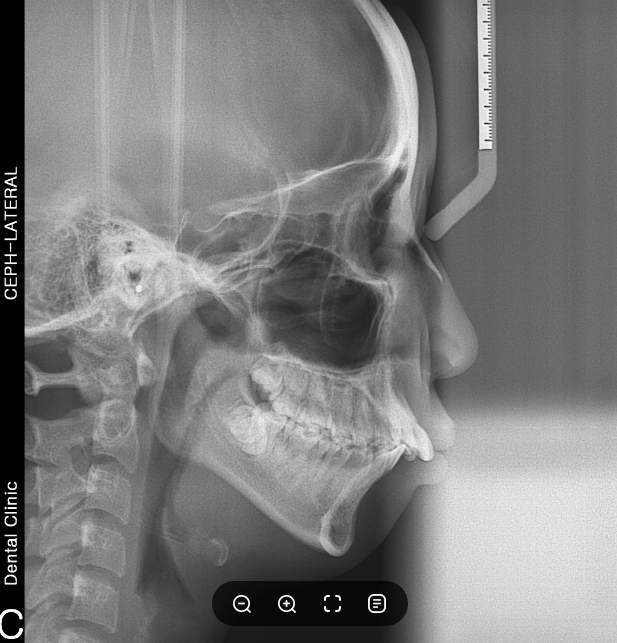

환자 분의 경우 상악 앞니가 많이 뻐드러진 케이스였습니다. 앞에서 볼 때는 잘 티가 나지 않지만 옆에서 봤을 때 뻐드러진 것을 확인할 수 있었는데요. 여기에 심한 무턱 증상을 동반하고 있었기 때문에 입이 힘을 주지 않을 때 다물어지지 않고 입술이 튀어나와보이는 증상을 갖고 있었습니다.

파노라마 사진을 보면 더 확연히 확인할 수 있죠. 앞니의 뻐드러짐과 돌출입, 무턱을 모두 개선할 수 있는 치아교정. 수술없이도 안모 변화가 크게 개선된 것을 보면 정말이지 뿌듯합니다. 환자분의 경우 치료 종료 후 8년이 지난 파노라마 사진으로도 교정 후 잘 유지되고 있다는 것을 확인할 수 있었는데요.